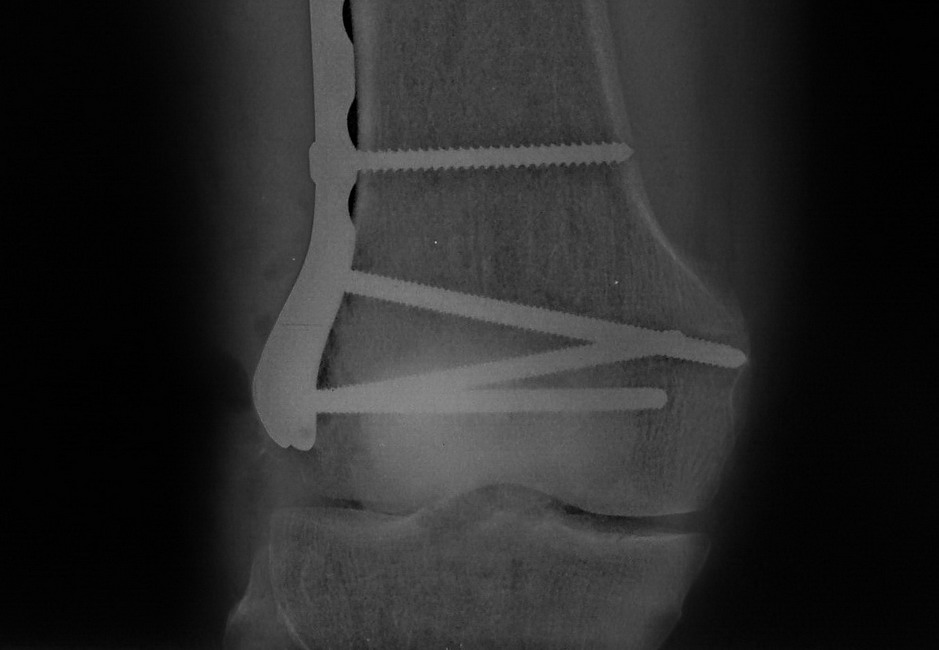

[Ortho] Нелеченный перелом Hoffa

Остеосинтез LCP пластиной